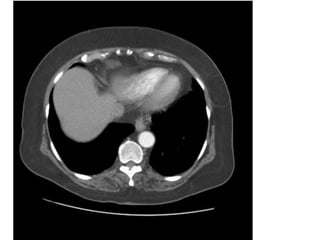

Case 6: bn nam nhập viện vì đau ngực, khó thở.

- Siêu âm: dãn thất (P) và tăng áp đm phổi.

- CT thấy huyết khối đm phổi (P). Dãn đm phổi gốc.

COPD. - Điều trị tại BVTMAG. (điều trị nội khoa bảo tồn).